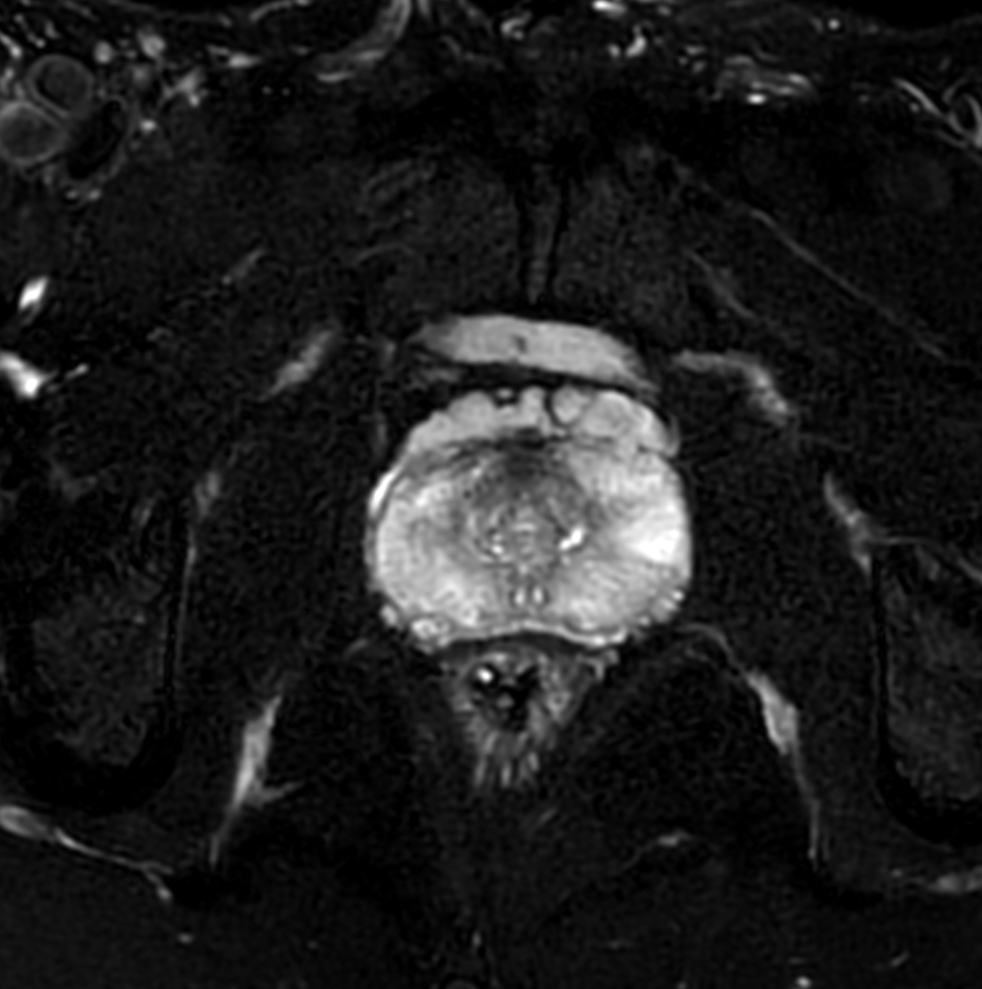

Prostate with dS ZOOM imaging

Aarhus University Hospital, Denmark